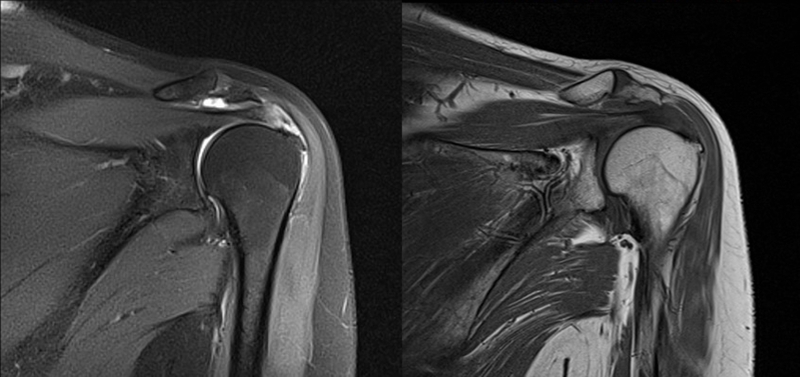

2、MRI检查

MRI目前是诊断肩袖疾病中最常用的检查,可以直观的观察肩袖肌腱。

图21 斜冠状位(临床常用)a.T2,b.T1

图22 斜矢状位 a.冈上肌出口,肩袖诊断不如斜冠状位;b.冈上肌及肌腹脂肪浸润成度,评估手术与否

图23 横断位a.正常肩胛下肌;b.肩胛下肌损伤

图24 a.肩袖全层撕裂;b.正常MRI